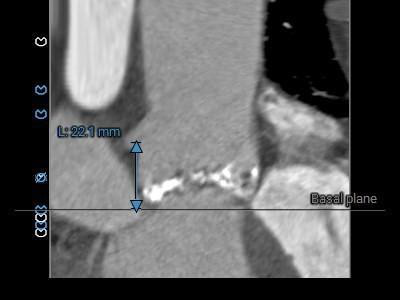

主动脉根部测量:

三叶式主动脉瓣,R-N疑似粘连,LVOT呈敞口型,非横位心。

三叶式主动脉瓣,R-N疑似粘连,重度钙化,分布于各窦内沿轴向延伸至窦底,无冠窦钙化延伸到LVOT水平;LVOT呈敞口型;